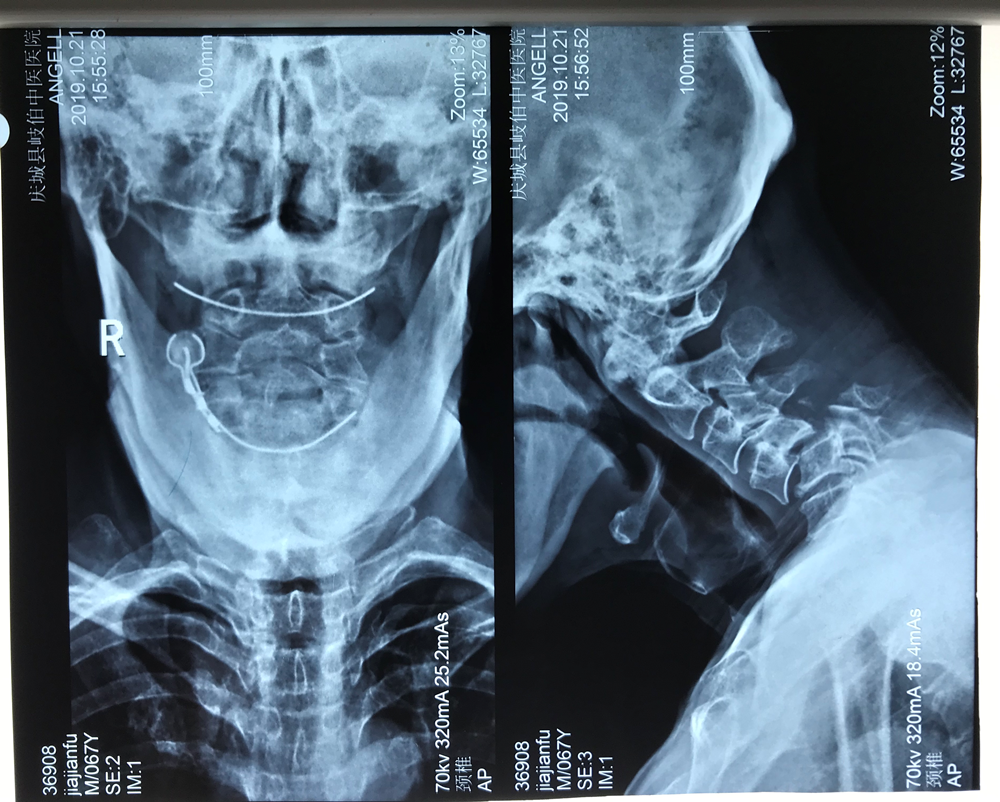

患者67歲,男性,在家勞作時不慎從高處摔下,頭部落地,致頸部受傷,受傷當(dāng)時即感覺頸部疼痛并有雙上肢麻木、活動受限,被家屬緊急送往當(dāng)?shù)蒯t(yī)院就診,相關(guān)檢查后明確診斷:頸4椎體完全性滑脫并頸5椎體骨折。因手術(shù)難度高,患者隨即轉(zhuǎn)診至我院骨一科就診?剖已杆俳M建救治團(tuán)隊,經(jīng)過縝密的術(shù)前討論,決定首先行顱骨牽引手術(shù),緩解患者神經(jīng)受壓癥狀,隨后根據(jù)患者情況細(xì)化手術(shù)方案——決定全麻下為患者一期行頸椎前后聯(lián)合入路切開減壓、脊髓探查、椎體滑脫復(fù)位內(nèi)固定手術(shù)治療。